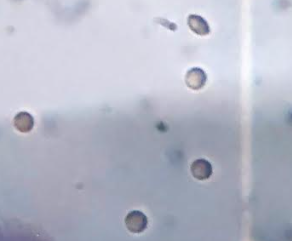

Hemolysis study

Hemolysis study helps to study the effect of the formulation on cell lysis, particularly RBC lysis. PPI dendrimers cause hemolysis due to terminal amine groups of dendrimers. The drug FPV also induces hemolytic anemia as reported by the Food and Drug Administration (FDA) [15]. The plain drug showed very high hemolytic activity (47.07±1.28%). The hemolytic tendency of the drug and dendrimer drastically changed on conjugation. Upon conjugation free drug was not available that reduces the toxicity and thus, RBCs lysis similarly the terminal amine group of dendrimers was occupied by the drug reducing its toxicity. Fig. 8 represents the % hemolysis data of the drug FPV, 5G PPI dendrimers, and three different concentrations of FPV-DEN.

The percentage hemolysis of the formulation was tested at three different levels, demonstrating that toxicity increased with the dose of the formulation [39-41]. The toxicity of the formulation increases as the formulation's concentration rises. At the formulation concentrations of 0.3, 0.6, and 0.9 µg/ml, the toxicity was found to be 5.45±0.99%, 12.12±1.25%, and 22.82±1.08% [22, 23]. RBCs were photographed after being exposed to various formulation concentrations, FPV, as well as saline and water. When RBCs were treated with 0.9% saline, the images revealed no lysis; however, full lysis was shown when RBCs were treated with water. The formulation at a lower concentration (0.3% µg/ml) does not show hemolysis, while hemolysis increases with increasing concentration. Fig. 9 represents the photograph of RBCs treated with saline, water, drug FPV, 5G PPI dendrimers, and FPV-DEN at 0.3%, 0.6%, and 0.9% µg/ml concentration.

(a) Saline (b) Water

(c) FPV (d) 5G PPI Dendrimers

(e) FPV-DEN (0.3 µg/ml) (f) FPV-DEN (0.6 µg/ml)

(g) FPV-DEN (0.9 µg/ml)

Fig. 9: Surface morphology of RBCs-(a) Saline, (b) Water, (c) Drug FPV, (d) 5G PPI dendrimers, (e) FPV-DEN (0.3 µg/ml), (f) FPV-DEN (0.6 µg/ml), and (g) FPV-DEN (0.9 µg/ml)